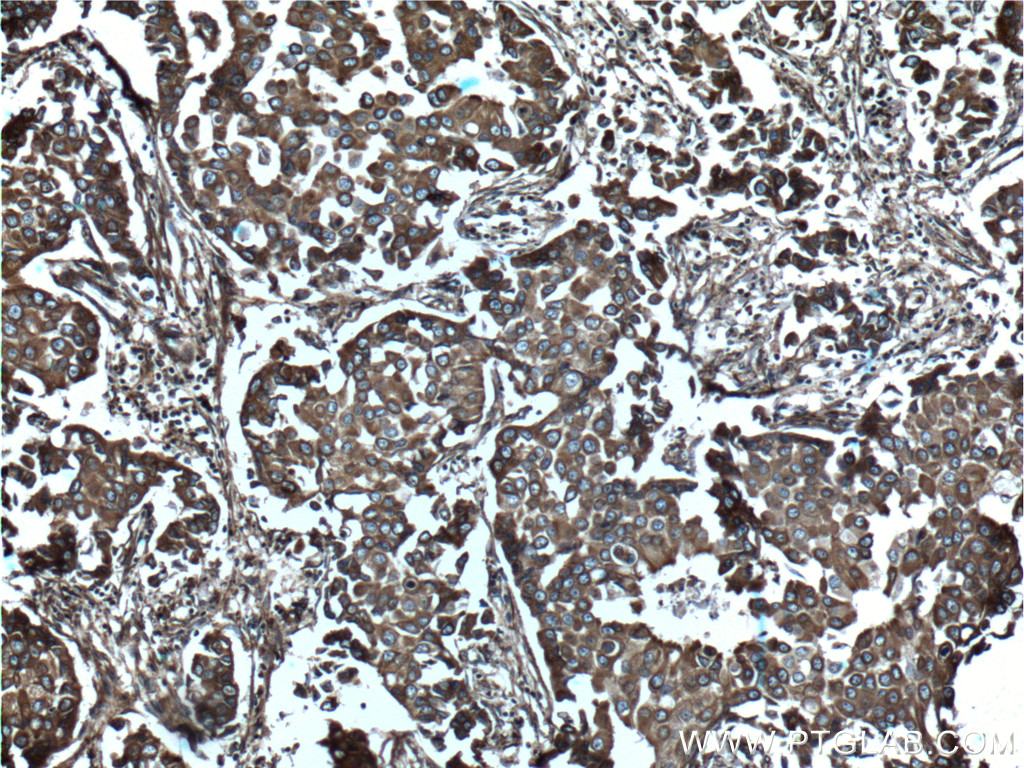

| Positive IHC detected in | human lung cancer tissue, human breast cancer tissue, human kidney tissue Note: suggested antigen retrieval with TE buffer pH 9.0; (*) Alternatively, antigen retrieval may be performed with citrate buffer pH 6.0 |

| Immunohistochemistry (IHC) | IHC : 1:50-1:500 |